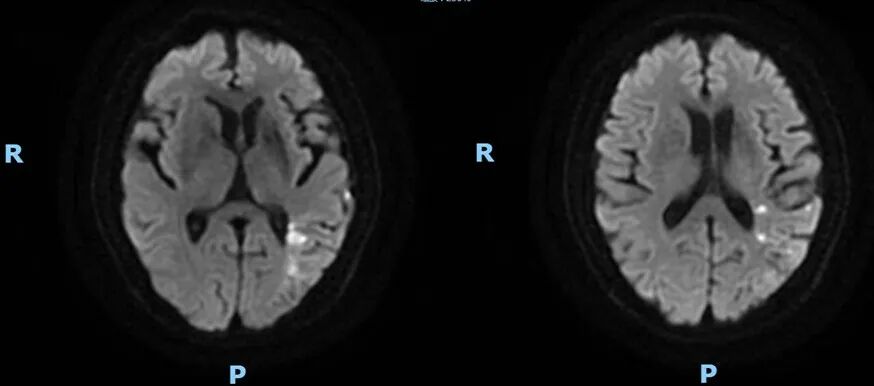

2021-6-25 颅脑DWI

重要影像结论:2021-6-25右侧基底节区新发脑梗死,2021-12-3提示右侧颈内动脉海绵窦段重度狭窄。

2022-7-17 颅脑DWI

2022-7-17 颅脑MRA

重要影像结论:右侧放射冠区新发脑梗死,右侧颈内海绵窦段重度狭窄,右侧大脑半球缺血。